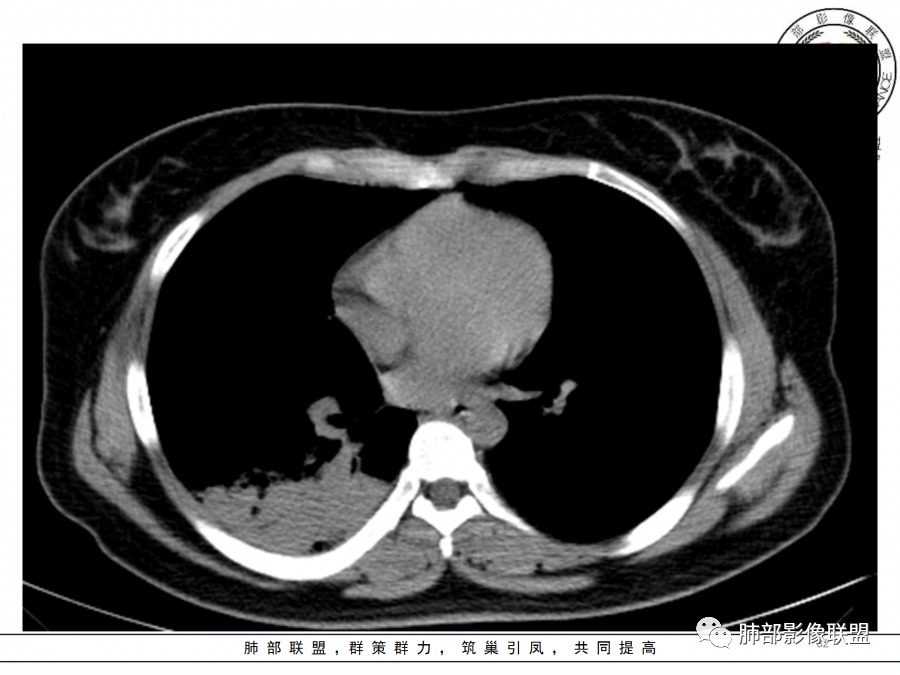

这个病变也不是一个起源中心,胸膜下,多发结节状、实变影。而大叶性肺炎多数由内-外大片状。所以是肺实质多发融合病变。单纯从影像上,还是比较符合隐球菌特点,胸膜下,多发、多中心,相互融合(兄弟齐心)。

隐球菌,胸膜下病灶,多个起源中心,最终还是融合在一起,侧向融合为主的。

隐球菌,侧向融合、外围胸膜下为主,也有累及叶段的、比较少。

隐球菌之顺口溜(影像征像版)在那遥远的边远山区——胸膜下生活着一群蘑菇兄弟——性质相同多结节表面虽脏,内心实诚——有晕,一般无空洞扮扮鬼脸,偶尔调皮——鬼脸征撞墙就跑,颇有灵性——一般不引起胸膜增厚积液气管通畅或进门才堵,只为空气——不会堵门口周围蔓延,不乱播散,死心踏地——不走淋巴,气管,血道播散。污头垢面,家里干净,只因免疫不低,神采奕奕——空洞干净,注意:以上不适用于免疫力低下病人。

1)实变影为大小不等多中心性。

2)沿胸膜下分布趋势(不同于大叶性肺炎的肺叶“造型”)。

3)周围较大范围磨玻璃影及小叶间隔增厚。

4)病灶体积增大明显(叶间裂推移)。